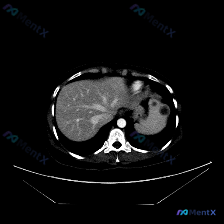

整理了一个近期看到的病例资料和分析思路,分享给大家。 --- 【基本影像信息 - 检查方法: 上腹部CT横断面(软组织窗) - 影像核心表现: - 图像质量良好,解剖结构显示清晰; - 肝脏形态大致正常,肝实质密度尚均匀; - 脾脏:形态饱满,实质内可见较大的类圆形低密度灶,边界尚可辨认,中心密度低...